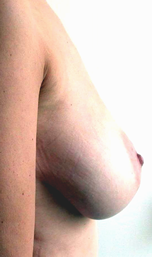

Cet album montre des exemples de réductions mammaires pour hypertrophie ptôse. On parle d’hypertrophie mammaire vraie lorsqu’on doit réaliser au moins l’ablation de 350 grammes de tissu par sein. Aucune des patientes ne présente en post-opératoire de cicatrice en T inversé. Toutes ont bénéficié de plasties de réductions à cicatrices courtes.